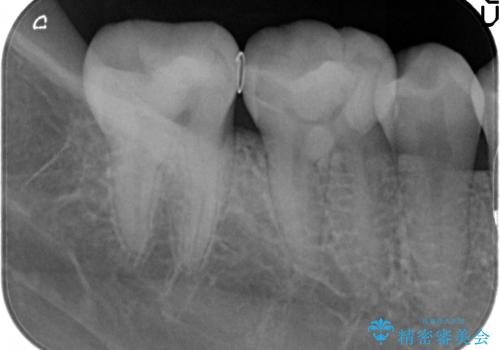

歯の神経を残す、丁寧な虫歯の除去

マイクロスコープ、拡大鏡を用いて治療を行うことで虫歯を取り切ることと必要以上に歯を削らず真剣を温存することのできる確率が高まります。

虫歯治療後の予後をより良くするために、虫歯を取り切ること精密な修復物の装着が必須となります。